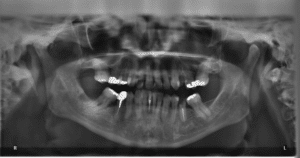

Developmental considerations add another layer to frequency decisions. Children ages 6-8 require monitoring for proper eruption of permanent first molars and incisors, while adolescents need assessment of wisdom tooth development and potential crowding issues. However, these developmental x-rays — typically panoramic images — are usually needed only once every 3-5 years unless specific problems arise.

The diagnostic benefits of pediatric dental x-rays extend far beyond simple cavity detection. X-rays reveal the development and positioning of permanent teeth while they’re still forming beneath the gums, allowing orthodontic intervention during optimal developmental windows. Early detection of impacted teeth, extra teeth, or developmental anomalies can prevent complex surgical procedures and extensive orthodontic treatment later.

Interproximal cavities — those developing between teeth where visual examination and probing cannot detect them — represent the most compelling case for routine radiographic screening. These lesions, particularly common in children due to tight tooth contacts and developing oral hygiene skills, can progress rapidly in primary teeth and affect the permanent teeth developing beneath them.